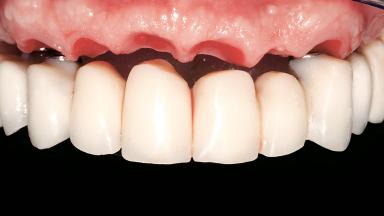

Immediate Loading of Six Implants in the Maxilla and Final Restoration with a Full-Arch CAD/CAM Zirconia FDP

A 63-year-old male patient was referred for a consultation and treatment of partial edentulism in the maxilla. The patient presented with residual anterior teeth and declined a partial removable prosthesis. He reported that the maxillary posterior teeth had been extracted due to mobility and periodontal disease two months before the consultation. The patient’s chief complaint was that his residual maxillary teeth were mobile and that he was unable to chew. The patient’s desire was a stable and comfortable fixed maxillary rehabilitation. The patient was a light smoker (fewer than 10 cigarettes/ day), and his medical history was without significant findings. He was not on any regular medication at the time of consultation. The extraoral examination revealed a normal physiognomy with a correct distribution of the facial thirds. The patient presented a low lip line, and the transition line between teeth and soft tissues was not exposed during a forced smile.

Prosthesis Type FDP

Defining Characteristics Fully edentulous upper jaw to be rehabilitated with an implant-borne fixed dental prosthesis

Loading Protocol Immediate